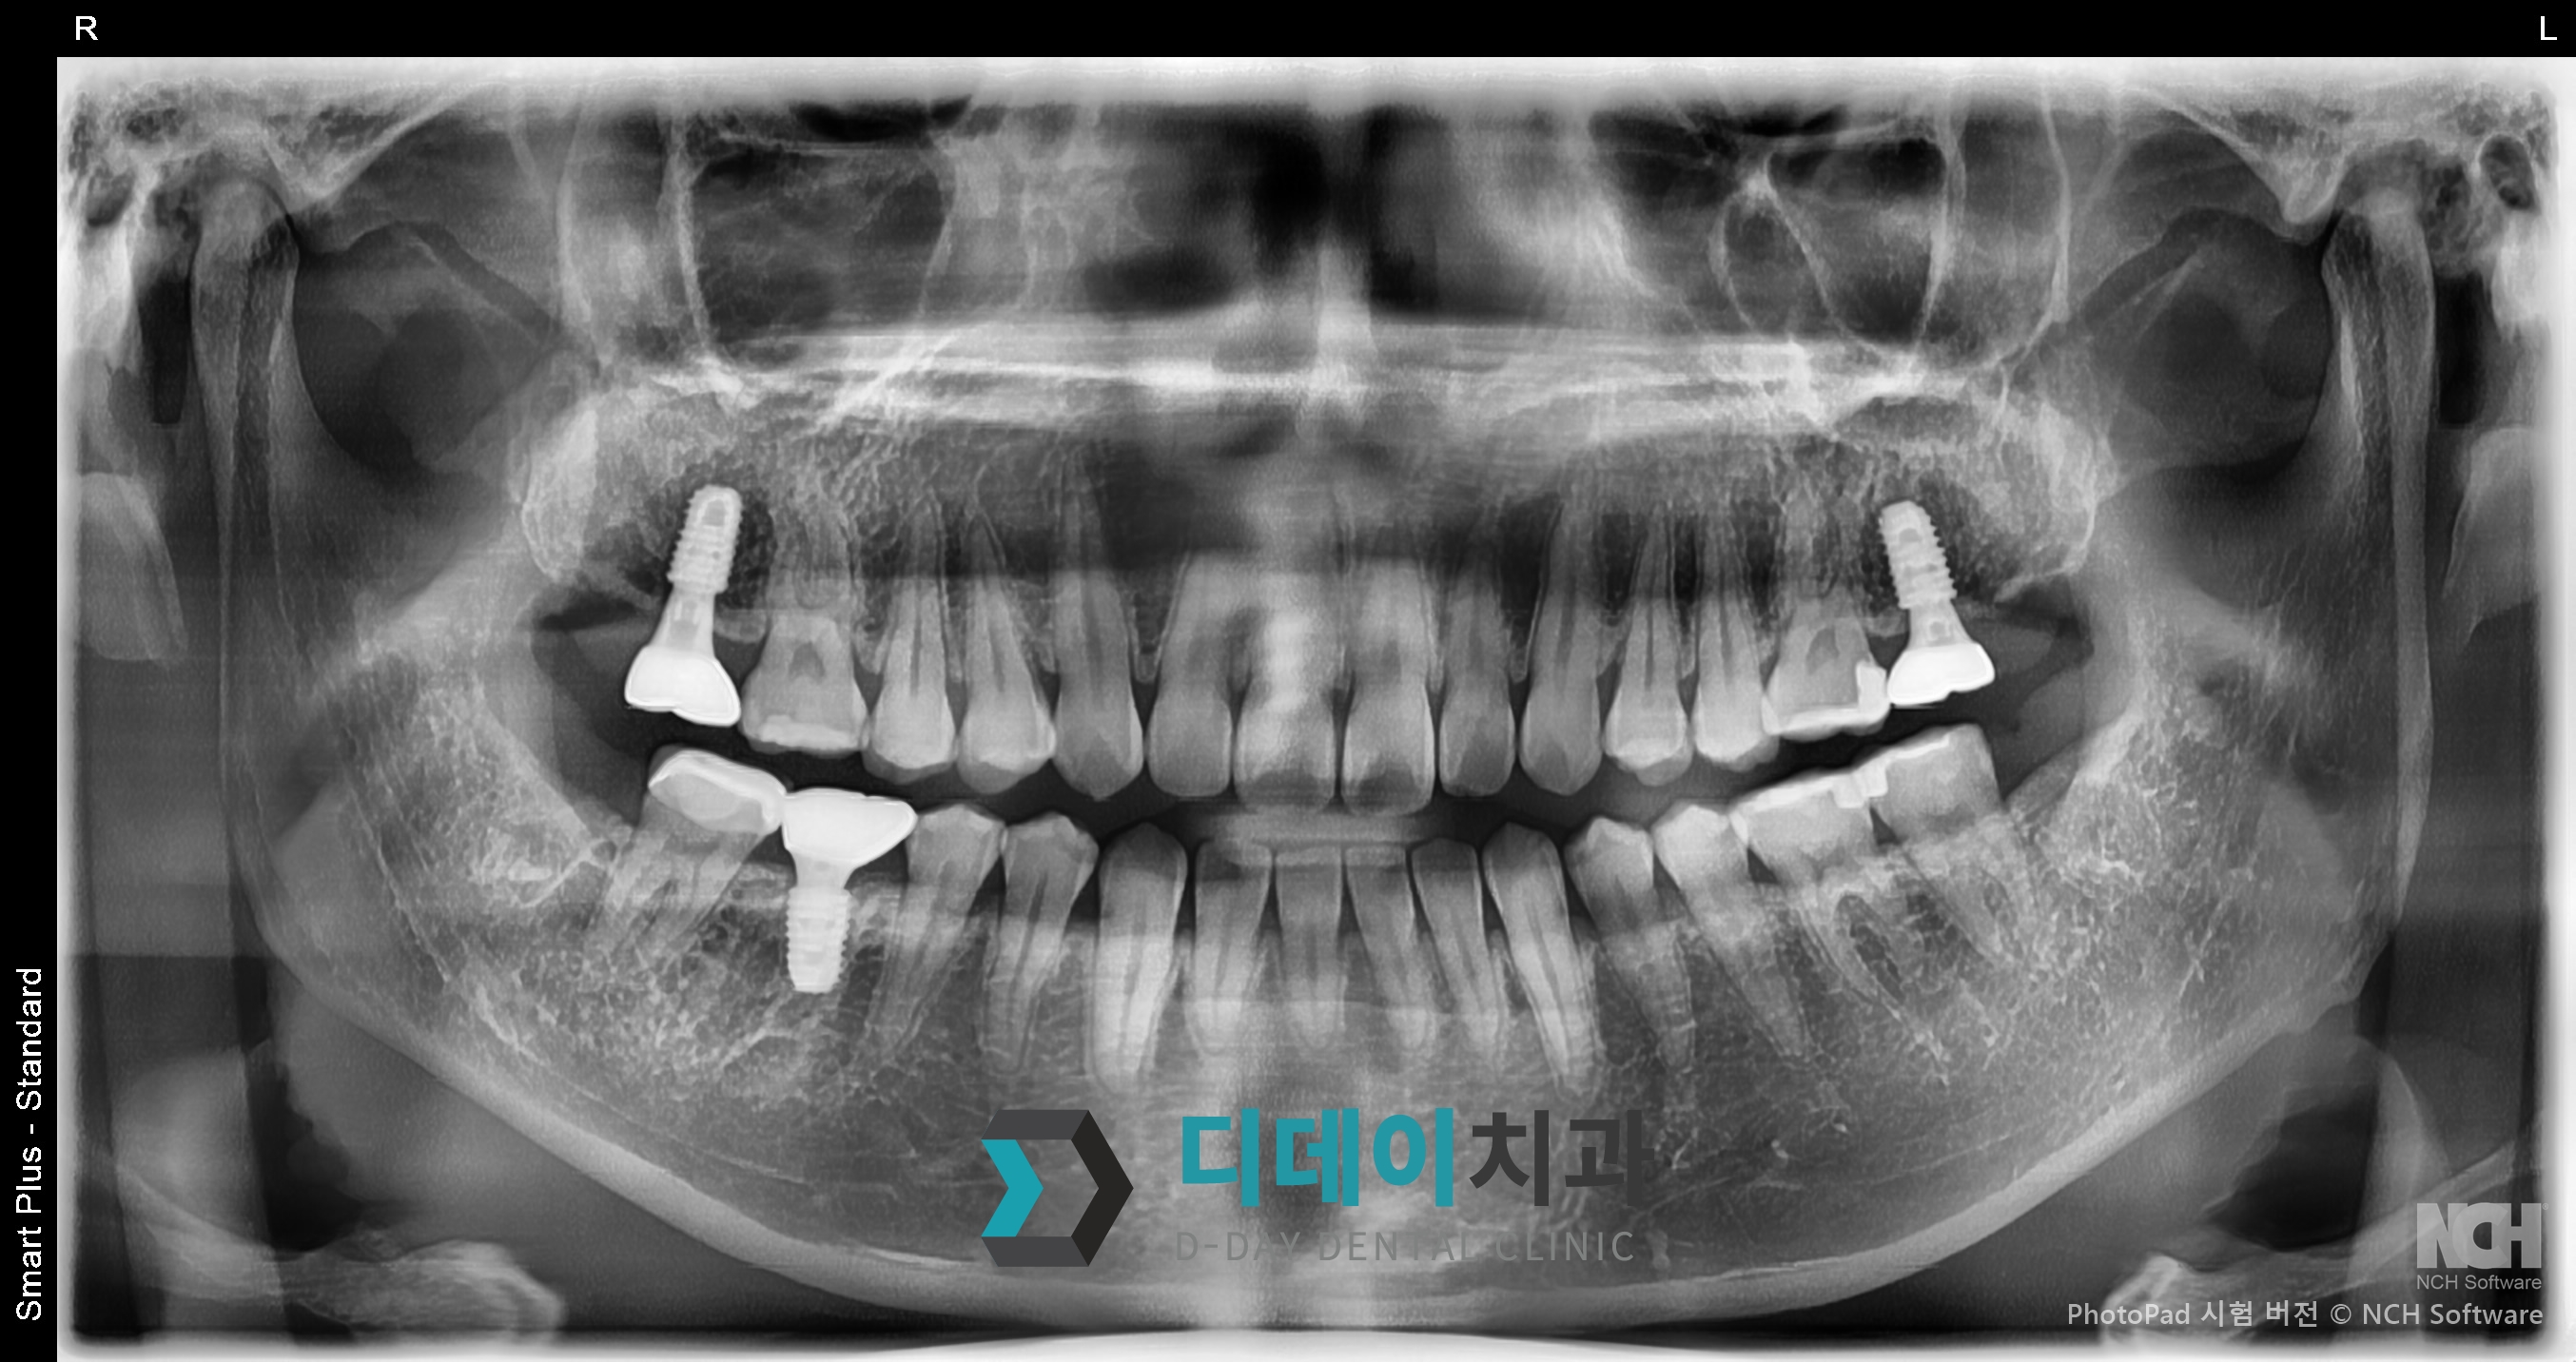

오른쪽 위아래 임플란트와 왼쪽 위 충치때문에 내원하신 환자분입니다.

왼쪽 위는 광범위한 충치로 인해 발치후 즉시 임플란트 식립을 진행했고 오른쪽 위아래 또한 임플란트 식립했습니다.